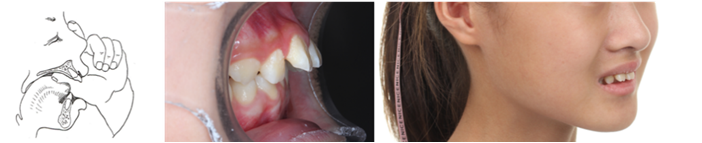

4.异常吮指习惯

拇指长期放置于上下前牙之间,上下前牙受压形成前牙开𬌗,长期吸吮动作增加颊肌对牙弓的压力,造成牙弓狭窄,腭盖高拱,上前牙拥挤前突,前牙深覆盖,开唇露齿等,且手指压下颌向后,日后可能出现下颌后缩畸形。

1.弹舌——训练舌肌力量,引导正确舌位

2.口香糖训练——精准训练舌位

3.抿嘴训练——训练唇肌闭合功能

4.吹气球训练——训练唇肌、颊肌功能